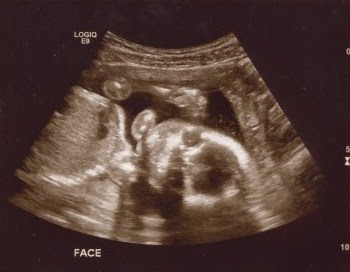

For an hour and a half today we watched, smiled, and cried at the images of our sweet baby boy. I learned a new kind of love today and my heart is full. I can't get enough of his little profile. We are so very blessed. Meet our little guy: